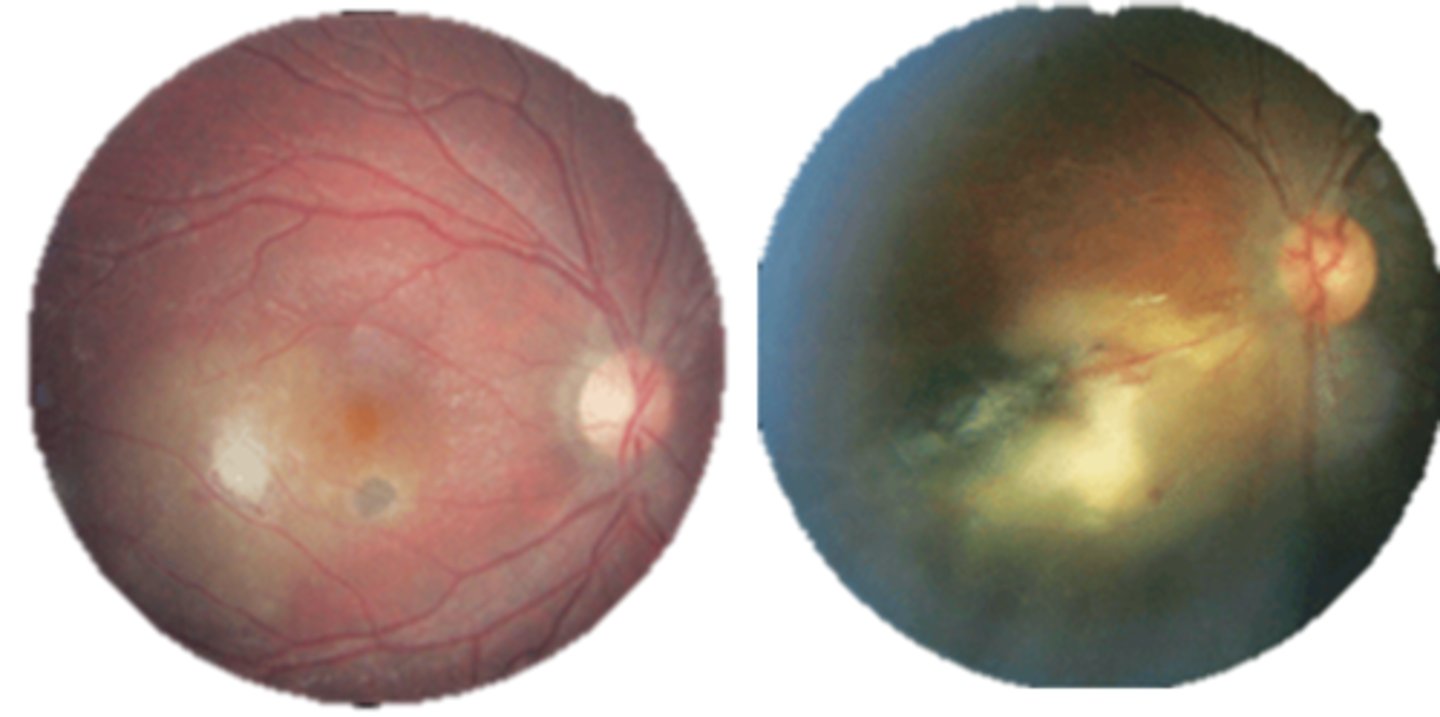

What finding of toxoplasmosis is seen in A/B?

retinitis turns into hazy scar with nerve pallor

What finding of toxoplasmosis is seen in C/D?

scarring overtime with VA loss/scotoma